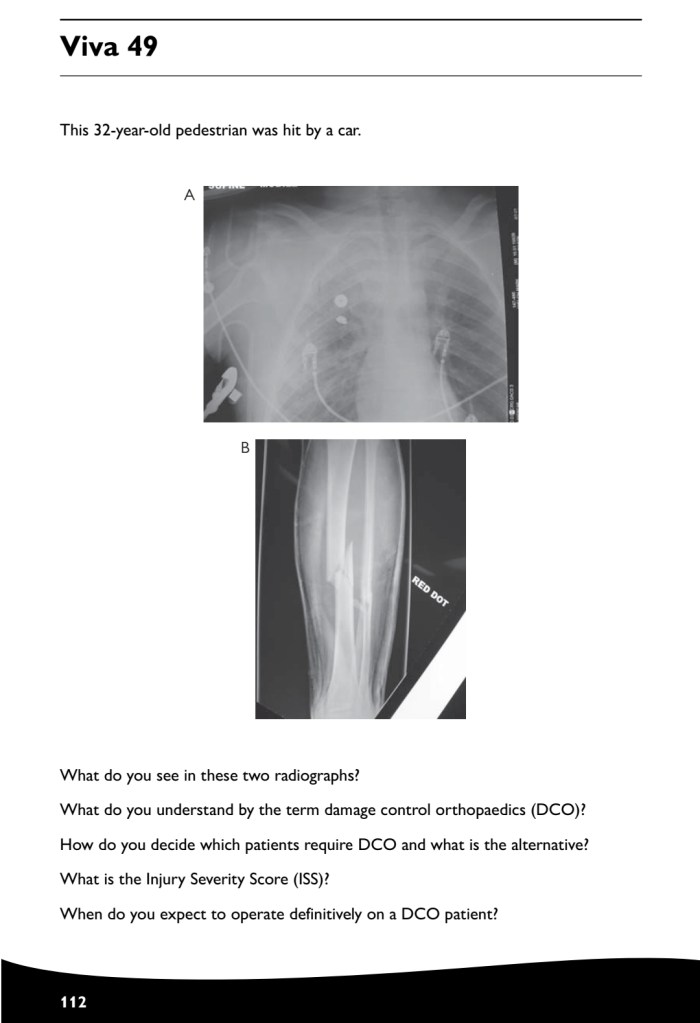

Revision how to answer your case